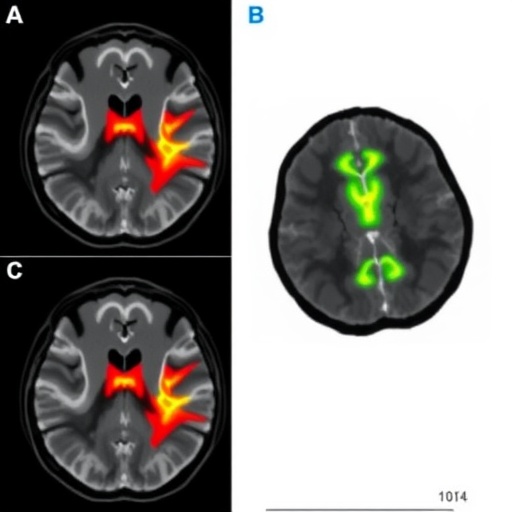

The research team embarked on a retrospective exploration, integrating conventional MRI modalities — T2-weighted imaging (T2WI), diffusion-weighted imaging (DWI), and apparent diffusion coefficient (ADC) maps — from a robust cohort of 264 patients diagnosed with prostate cancer. These diverse imaging techniques offer complementary insights, capturing structural, cellular, and microenvironmental tumor attributes, essential for comprehensive radiomic analysis.

Central to their approach was the concept of habitat imaging (HI), which partitions tumors into distinct microenvironmental subregions, or habitats, illuminating the spatial variation within the malignancy. This paradigm shift enables the quantification of intratumoral heterogeneity (ITH) via advanced radiomic features extracted from these habitats, transcending traditional whole-tumor analyses that often overlook subtle but clinically significant variations.